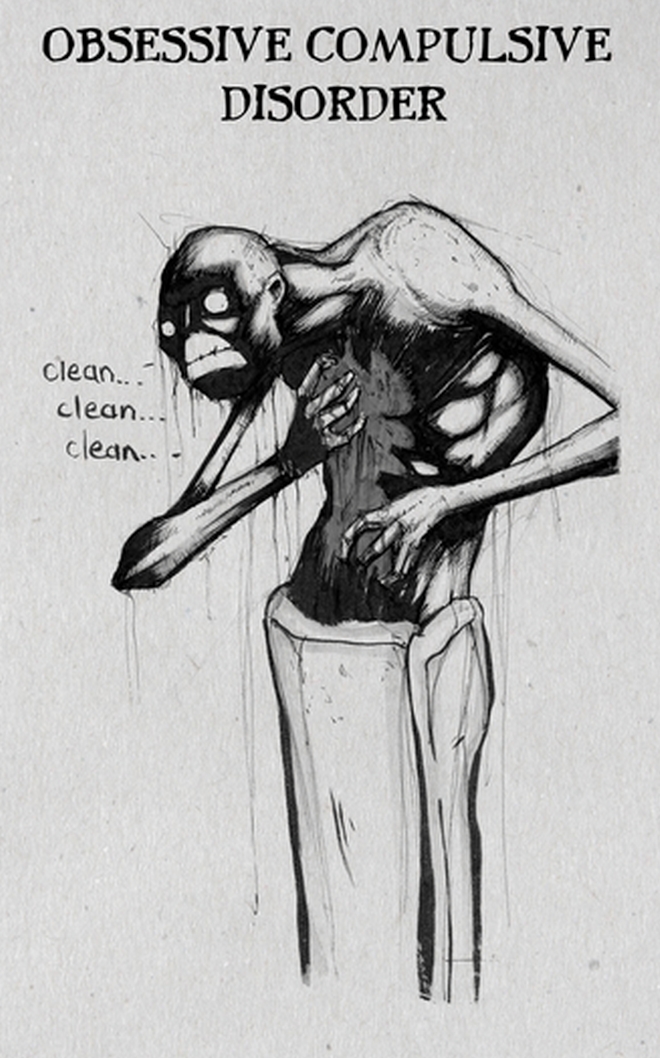

Έχω δεχτεί και αρνητικές αντιδράσεις για τα σκίτσα του αυτισμού και του ψυχαναγκασμού: Μου είπαν ότι οι εικαστικές επιλογές που έκανα (πχ στον ψυχαναγκασμό επέλεξα την εμμονή με την καθαριότητα) είναι στερεοτυπικές, ωστόσο εξήγησα ότι ο στόχος μου ήταν να δείξω τις πιο αντιπροσωπευτικές συμπεριφορές μέσα από μία μόλις εικόνα.

Ιδεοψυχαναγκαστική διαταραχή